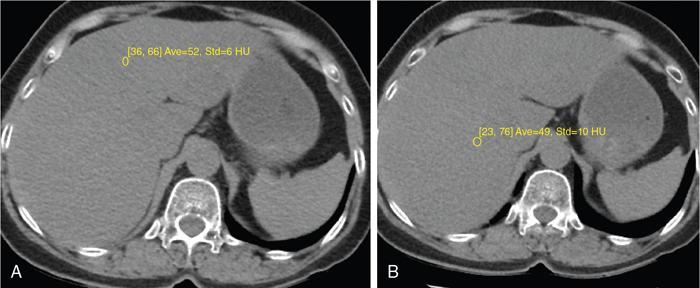

Excessive triglyceride accumulation within hepatocytes is defined as hepatic steatosis. Major conditions associated with hepatic steatosis include alcoholic fatty liver disease (AFLD) and nonalcoholic fatty liver disease (NAFLD). Causes of hepatic steatosis are discussed in Table 9.10.3. NAFLD is the most common form of hepatic steatosis and discussed in detail below. Up to 90% of patients with chronic alcoholic intake have fatty liver. Those with pure AFLD have a 10% risk of progressing to cirrhosis. Consumption of 30 g ethanol/day shows increased risk of chronic liver disease and cirrhosis. Other risk factors include female sex, obesity, cigarette smoking, obesity and associated risk factors. These factors are divided into 2 main categories which can cause fatty liver: inborn errors of metabolism and acquired metabolic disorders. Inborn errors of metabolism include abetalipoproteinemia, galactosemia, glycogen storage disease, hereditary fructose intolerance, homocystinuria and Wilson disease. Inflammatory bowel disease, jejunoileal bypass, malnutrition, starvation and total parenteral nutrition are acquired metabolic factors associated with increased risk. Chronic HCV infection, is associated with hepatic steatosis, with prevalence of 40%–80%. Hepatic steatosis can be seen as an adverse reaction to some medications such as tetracycline, valproic acid, some of chemotherapeutic agents, dexamethasone, amiodarone, methotrexate, tamoxifen and acetylsalicylic acid. Either microvesicular or macrovesicular steatosis can be observed in drug-induced hepatic steatosis. It generally occurs with therapy lasting several weeks or months and is reversible after discontinuation. The leading cause of hepatic steatosis in paediatric population is NAFLD. Six per cent of these patients develop cirrhosis and end-stage disease. Other less common causes include starvation and malnutrition, drugs (glucocorticoids, oestrogens, tetracyclines, and methotrexate), intoxications (carbon tetrachloride, organic phosphates, organic solvents, and alcohol), metabolic disorders, hepatitis C infection, and total parenteral nutrition. NAFLD is defined as steatosis affecting >5% of hepatocytes in the absence of a secondary cause. NAFLD represents a spectrum of disease, ranging from simple steatosis to steatohepatitis through to fibrosis and cirrhosis and in some cases hepatocellular carcinoma. NAFLD is a growing epidemic worldwide in part due to obesity and insulin resistance leading to liver accumulation of triglycerides and free fatty acids. Nonalcoholic steatohepatitis (NASH) is defined by histologic terms as a necroinflammatory process whereby the liver cells become injured in a background of steatosis. 20% of patients with NAFL progress to NASH, which progresses to fibrosis and cirrhosis over a 15-year time period (Fig. 9.10.3). The definition of NAFLD requires imaging or histology evidence of steatosis and no causes for secondary hepatic fat accumulation like significant alcohol intake, drugs or hereditary disorders (Table 9.10.4). The incidence of NAFLD ranges from 20% to 30% in Western countries and 5%–18% in Asia. As it currently stands, NAFLD represents the second most common reason to be listed for a liver transplant. The prevalence of NAFLD is higher in patients with obesity, diabetes, and patients with hyperlipidaemia. Prevalence increase with age from less than 20% at age 20 to more than 40% over 60 years of age. Males show a higher risk for progression to NASH and fibrosis (Table 9.10.5). Up to 90% of patients with NAFLD have simple steatosis, and about 30% of patients with NAFL develop NASH, and in again about 30%–40% of NASH patients the disease progresses to manifest fibrosis and cirrhosis NAFLD related cirrhosis has a 10-year mortality of 25% and a 5% chance of developing end-stage liver disease and HCC. The theory implicated in the pathogenesis of NAFLD is the two-hit theory. Insulin resistance, enhanced dietary influx and increased hepatic lipogenesis leading to accumulation of triglycerides (TG) and FFA in the hepatocytes is the first hit. The lipid peroxidation, mitochondrial dysfunction and inflammation resulting in hepatocyte damage and development of liver fibrosis is the second hit. The stages of NAFLD on histology range from steatosis initially to hepatic fibrosis in late stages. In the steatotic stage large (macro-) and small (micro-) vesicles of fat, predominately triglycerides, accumulate within hepatocytes. The affected parenchyma is divided into thirds: 5%–33%, 34%–66% and >66% and graded as mild, moderate and respectively. Ballooned hepatocytes with accompanied steatosis and inflammation are characteristic of the steatohepatitis stage. Fibrosis has a characteristic appearance with early lesions showing a perisinusoidal deposition followed by periportal fibrosis which progresses to bridging. Raised GGT is the most common liver enzyme elevated in NAFLD. Transaminases are within normal range in 80% patients. No specific blood tests can diagnose NAFLD. Liver biopsy has remained the gold standard for diagnosis and quantification of liver fat. Drawbacks, however, include invasive nature, sampling error and procedure related complications like bleeding. Various imaging techniques are currently available in diagnosing and quantifying liver fat. MRI in particular proton density imaging and MR Spectroscopy have revolutionized imaging of fatty liver. Normal liver parenchyma is the same as or slightly more echogenic than the adjacent kidney and spleen. Fat deposition leads to increased echogenicity of liver. Decreased beam attenuation in patients with fatty change leads to poor visualization of structures such as intrahepatic vessels, bile ducts and liver lesions and in severe cases diaphragm (Table 9.10.6). Fatty liver can be graded on USG as: US has a fair accuracy of detecting the moderate to severe hepatic steatosis with sensitivity of about 90% and specificity of about 95% for patients without concomitant chronic liver disease. Ultrasound is observer and equipment dependent. Confounding factors such as large body hiatus may lead to overestimation of hepatic steatosis due to beam attenuation by overlying fat. Conditions like fibrosis, inflammation can affect interpretation. The ratio between the mean brightness level of liver and right kidney is called the Hepatorenal sonographic index. A cut off of 1.49 has a high sensitivity and specificity for diagnosis of steatosis >5%. The main advantages of CT for assessing steatosis are relatively fast acquisition, ease of performance, and quantitative results. Estimation of fatty liver is done on non-contrast enhanced images. The normal liver density is around 60 HU, which is approximately 10 HU higher than normal spleen. Fat accumulation in the liver manifests as proportionate decrease in density. Both the absolute and relative (to the spleen) values are used to characterize steatosis; a cut-off value of 40 HU has been suggested to predict fat content greater than 30% (Figs. 9.10.6 and 9.10.7) Attenuation difference between liver and spleen on unenhanced CT scan is a commonly used quantitative parameter to evaluate hepatic steatosis. This avoids errors in attenuation value measurement from different CT scanners and different reconstruction algorithms. Normal liver parenchymal attenuation on nonenhanced CT is slightly higher than the spleen. Liver attenuation progressively decreases as percentage steatosis increases (Table 9.10.7) (Fig. 9.10.8) Methods of liver fat quantification on CT have been discussed in details in chapter on liver transplant. Limited diagnostic accuracy for detecting mild degree hepatic steatosis is one of major drawback of CT. Disorders causing hyperdensity of liver such as iron, glycogen deposition can lead to errors in interpretation. The concomitant presence of iron and fat may not be accurately diagnosed on CT. Low CT density values may also be caused by oedema and inflammation. Likewise, the spleen is an imperfect reference standard as it can be affected by haemosiderosis and haemochromatosis in a small minority of patients. Dual-energy CT with its ability to perform material decomposition is more accurate in quantifying hepatic steatosis and allows staging of fibrosis. Imaging is done with two different energies (typically 80 kVp and 140 kVp). DECT has the potential to quantitate liver fat content independent of ROI (region of interest) placement. Magnetic resonance imaging (MRI) is presently the most accurate imaging modality for the evaluation of hepatic steatosis. Several different methods have been developed and introduced in MRI for the evaluation of hepatic steatosis. In this technique typically, two gradient echoes are acquired, one employing a TE in which the water peak (4.7 ppm) and the dominant fat peak (1.3 ppm) are ‘out of phase’ and hence subtractive (SOP), and the other using a TE in which the two peaks are ‘in phase’ and therefore additive (SIP). Because two echoes are acquired, this is often called ‘dual-phase’ or ‘dual echo’ imaging. Fat Signal Percentage is calculated as [SIP – SOP]/[2 × SIP] ×100. The dynamic range of magnitude based chemical shift techniques has typically a 0%–50% signal fat-fraction (Fig. 9.10.9) This technique uses both magnitude and phase information from three or more images acquired at different echo times appropriate for more accurate separation of water and fat signals as against only magnitude information in dual-echo. These methods provide estimates of fat fraction with a dynamic range of 0%–100%. Proton density Fat fraction (PDFF) is calculated as Sf/(Sw + Sf) where Sw = SI of the water component, Sf = SI of the fat component. PDFF specifically reflects the concentration of triglycerides in the hepatocytes as lipids within the other structures such as cell membranes and organelles are occult. Sensitivity up to 96% and specificity up to 100% for detecting any degree of steatosis have been reported. A fat-fraction threshold of 5.56% is commonly used to define steatosis; however, the optimal cut-off value still needs to be defined (Figs. 9.10.10 and 9.10.11). MRS can directly measure the chemical composition within tissue based on the frequency composition of the signal originated from the voxel of interest. Water proton peak appears as a single peak at 4.7 ppm, whereas fat peaks appear as multiple peaks around 1.3 ppm. PDFF can be calculated as the ratio of the sum of the signal intensities derived from the protons in fat divided by the sum of the signal intensities originated from the protons in both fat and water (Fig. 9.10.12). TABLE 9.10.8 MRS data are usually obtained from a single voxel manually placed in the liver parenchyma usually right posterior segment of the liver. Reported MRS sensitivities and specificities for detection of mild hepatic steatosis are 80.0%–91.0% and 80.2%–87.0%, respectively, outperforming CT and US. MRS can also provide excellent reproducibility of measurement. It is also unaffected by confounding factors like fibrosis, iron overload and glycogen. Small sample volume usually less than 3 × 3 × 3 cm3 is a major limitation of MRS, particularly in patients with uneven fatty change. Despite these practical limitations, MRS is considered to be the gold standard MR method for hepatic fat quantification. This is the most frequently encountered pattern and considering the homogenous involvement poses no diagnostic dilemma. Focal fat deposition and focal sparing in diffuse fatty liver are less common. These usually occur in specific locations like adjacent to falciform ligament or ligamentum venosum, in portal hepatis or gallbladder fossa. Imaging findings are suggestive of fatty pseudolesions rather than true masses. Occurrence in characteristic locations, absence of mass effect on vessels and structures, geographic configuration and contrast enhancement similar to or less than adjacent liver (Fig. 9.10.13). Fat deposition around insulinoma metastasis can occur as a local effect of insulin on the liver parenchyma. On ultrasound, it appears as an echogenic rim shows signal drop on out of phase images. Eisenberg has reported perilesional steatosis around focal nodular hyperplasia. Sometimes multiple small foci and seen scattered throughout the liver. These may appear as small round nodules (Fig. 9.10.14). Opposed phased imaging is more useful than CT or US to establish diagnosis. These may, however, pose a diagnostic dilemma in patients with known malignancy. Perivascular fatty infiltration is a recently described entity, mostly seen in alcoholic patients. This pattern is characterized by halos of fat that surround the hepatic veins, the portal veins, or both hepatic and portal veins (Fig. 9.10.15). Normal vessels coursing through the lesion without attenuation in calibre suggest the diagnosis. Peritoneal dialysis with insulin in the dialysate in patients with renal failure and insulin-dependent diabetes. Exposure of subcapsular hepatocytes to a higher concentration of insulin results in fat deposition in the subcapsular regions. Some hepatic lesions such as hepatic adenoma, hepatocellular carcinoma, regenerative nodules and focal nodular hyperplasia can show intracellular steatosis (Fig. 9.10.16). These areas show signal drop on opposed phase. However, postcontrast imaging characteristics of these lesions allow differentiation from areas of focal steatosis. Perilesional sparing has been reported in haemangioma and hepatocellular carcinomas. This may mainly represent decreased portal flow due to either compressed or atrophic hepatocyte cords in expanding metastases or arterioportal perfusion abnormalities in haemangiomas. The differential diagnosis of focal fat infiltration is discussed in Table 9.10.9. Accurate history and chemical shift imaging showing signal drop help in differentiation of focal fat from metastasis. These are visible only during the arterial and portal venous phases after contrast agent administration. The morphologic appearance of fat deposition and perfusion abnormalities is similar. Perfusion abnormalities however are visible only during the arterial and portal venous phases (Fig. 9.10.17). They are not seen as an attenuation difference on nonenhanced CT. Periportal oedema, inflammation, haemorrhage and lymphatic dilatation may mimic perivascular fat. With the exception of haemorrhage all other conditions affect periportal region symmetrically (Fig. 9.10.18). Patients with haemorrhages may show other signs of injury. Chemical shift imaging is helpful in cases with diagnostic challenges.

CT

Liver attenuation index

Principle: Fat has low attenuation a proportionate decrease in density is seen with increasing fat accumulation in liver

Assessment of hepatic steatosis using CT is based on the measurement of attenuation value of liver parenchyma, expressed as Hounsfield units (HU)

Attenuation difference between liver and spleen on unenhanced CT scan has been the most commonly used

Cut-off value of attenuation difference to detect moderate to severe degree hepatic steatosis-9